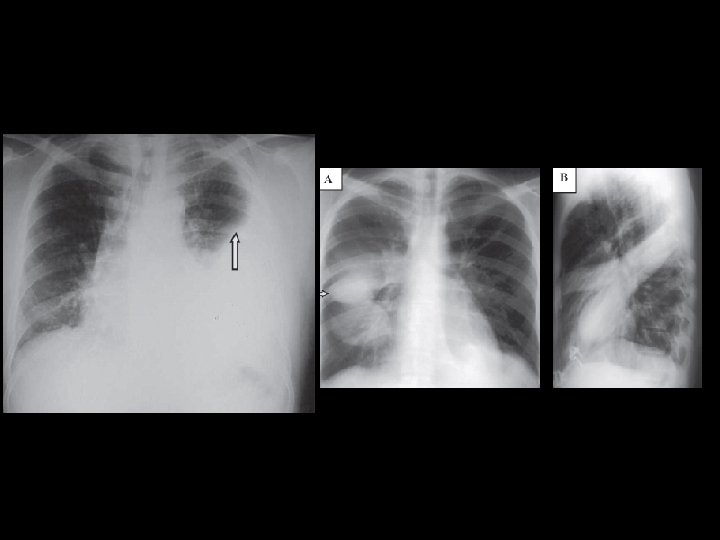

CASO CLÍNICO – PARTE IV “O paciente é medicado e submetido a uma correção cirúrgica, sendo o procedimento realizado com sucesso. Enquanto está na recuperação, inicia quadro de tosse produtiva, febre, dor torácica e dispneia. Ao exame físico apresenta Tax: 39, 2ºC, apresenta aumento do fremito toracovocal, macicez a percussão e estertores crepitantes em base pulmonar esquerda, com presença de broncofonia. Ausculta cardíaca está sem alterações. Foi solicitada radiografia de tórax PA e perfil (imagens abaixo). ”

CONGESTÃO PULMONAR Rx AP – (A) acentuação da trama vascular em ápices até periferia e aumento do tronco da artéria pulmonar; (B) alteração vascular + aumento da área cardíaca e derrame cisural a D; (C) caso mais grave com acometimento alveolar

EDEMA AGUDO DE PULMÃO Edema pulmonar cardiogênico. Aumento da área cardíaca, associado a velamento de padrão radiológico alveolar, com distribuição periilar, mais acentuado à direita.